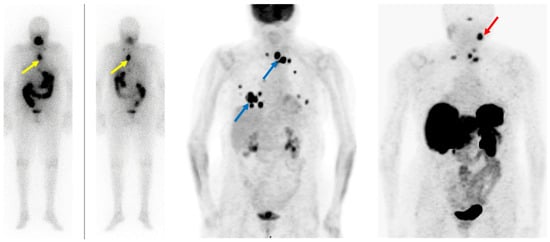

- Feine, U.; Lietzenmayer, R.; Hanke, J.P.; Wohrle, H.; Muller-Schauenburg, W. 18FDG Whole-Body PET in Differentiated Thyroid Carcinoma. Flipflop in Uptake Patterns of 18FDG and 131I. Nuklearmedizin 1995, 34, 127–134. [Google Scholar] [CrossRef]

- Feine, U.; Lietzenmayer, R.; Hanke, J.P.; Held, J.; Wöhrle, H.; Müller-Schauenburg, W. Fluorine-18-FDG and Iodine-131-Iodide Uptake in Thyroid Cancer. J. Nucl. Med. 1996, 37, 1468–1472. [Google Scholar]

- Liu, M.; Cheng, L.; Jin, Y.; Ruan, M.; Sheng, S.; Chen, L. Predicting 131I-Avidity of Metastases from Differentiated Thyroid Cancer Using 18F-FDG PET/CT in Postoperative Patients with Elevated Thyroglobulin. Sci. Rep. 2018, 8, 4352. [Google Scholar] [CrossRef]